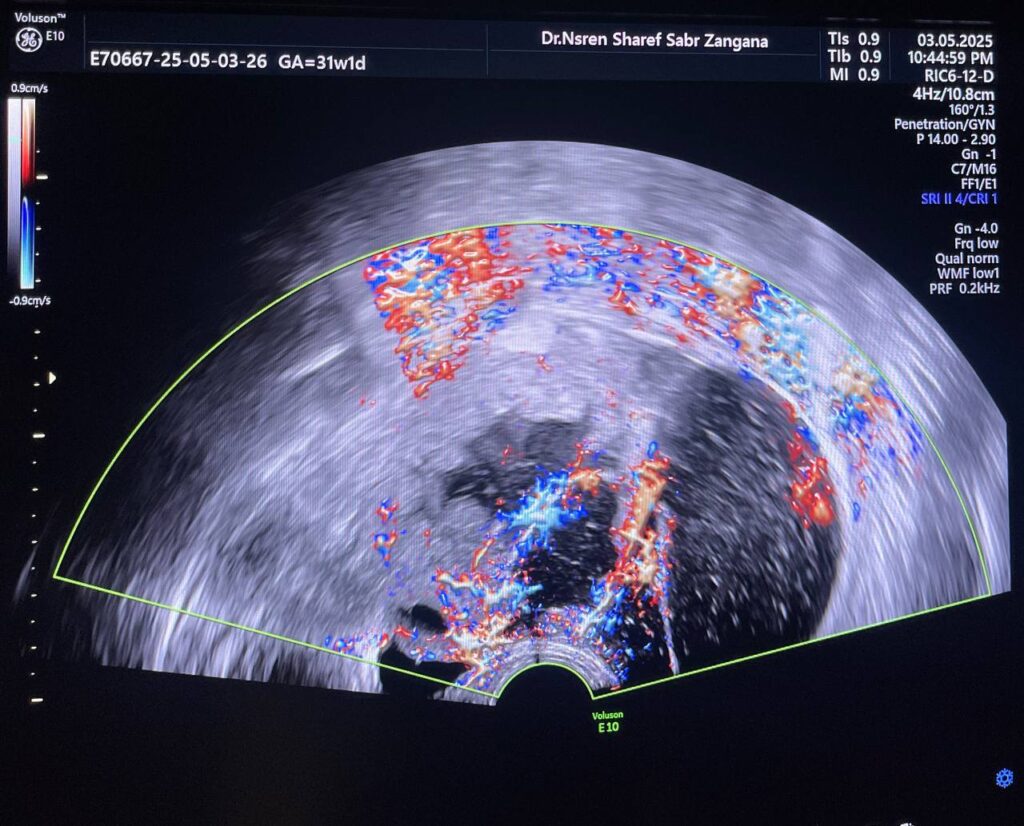

Right ovarian multilocular vascular (score 3) mass size about 107x71mm , no extension to surrounded tissue , nor lymph node , nor ascitis , Border line ovarian tumor ?? please for further study